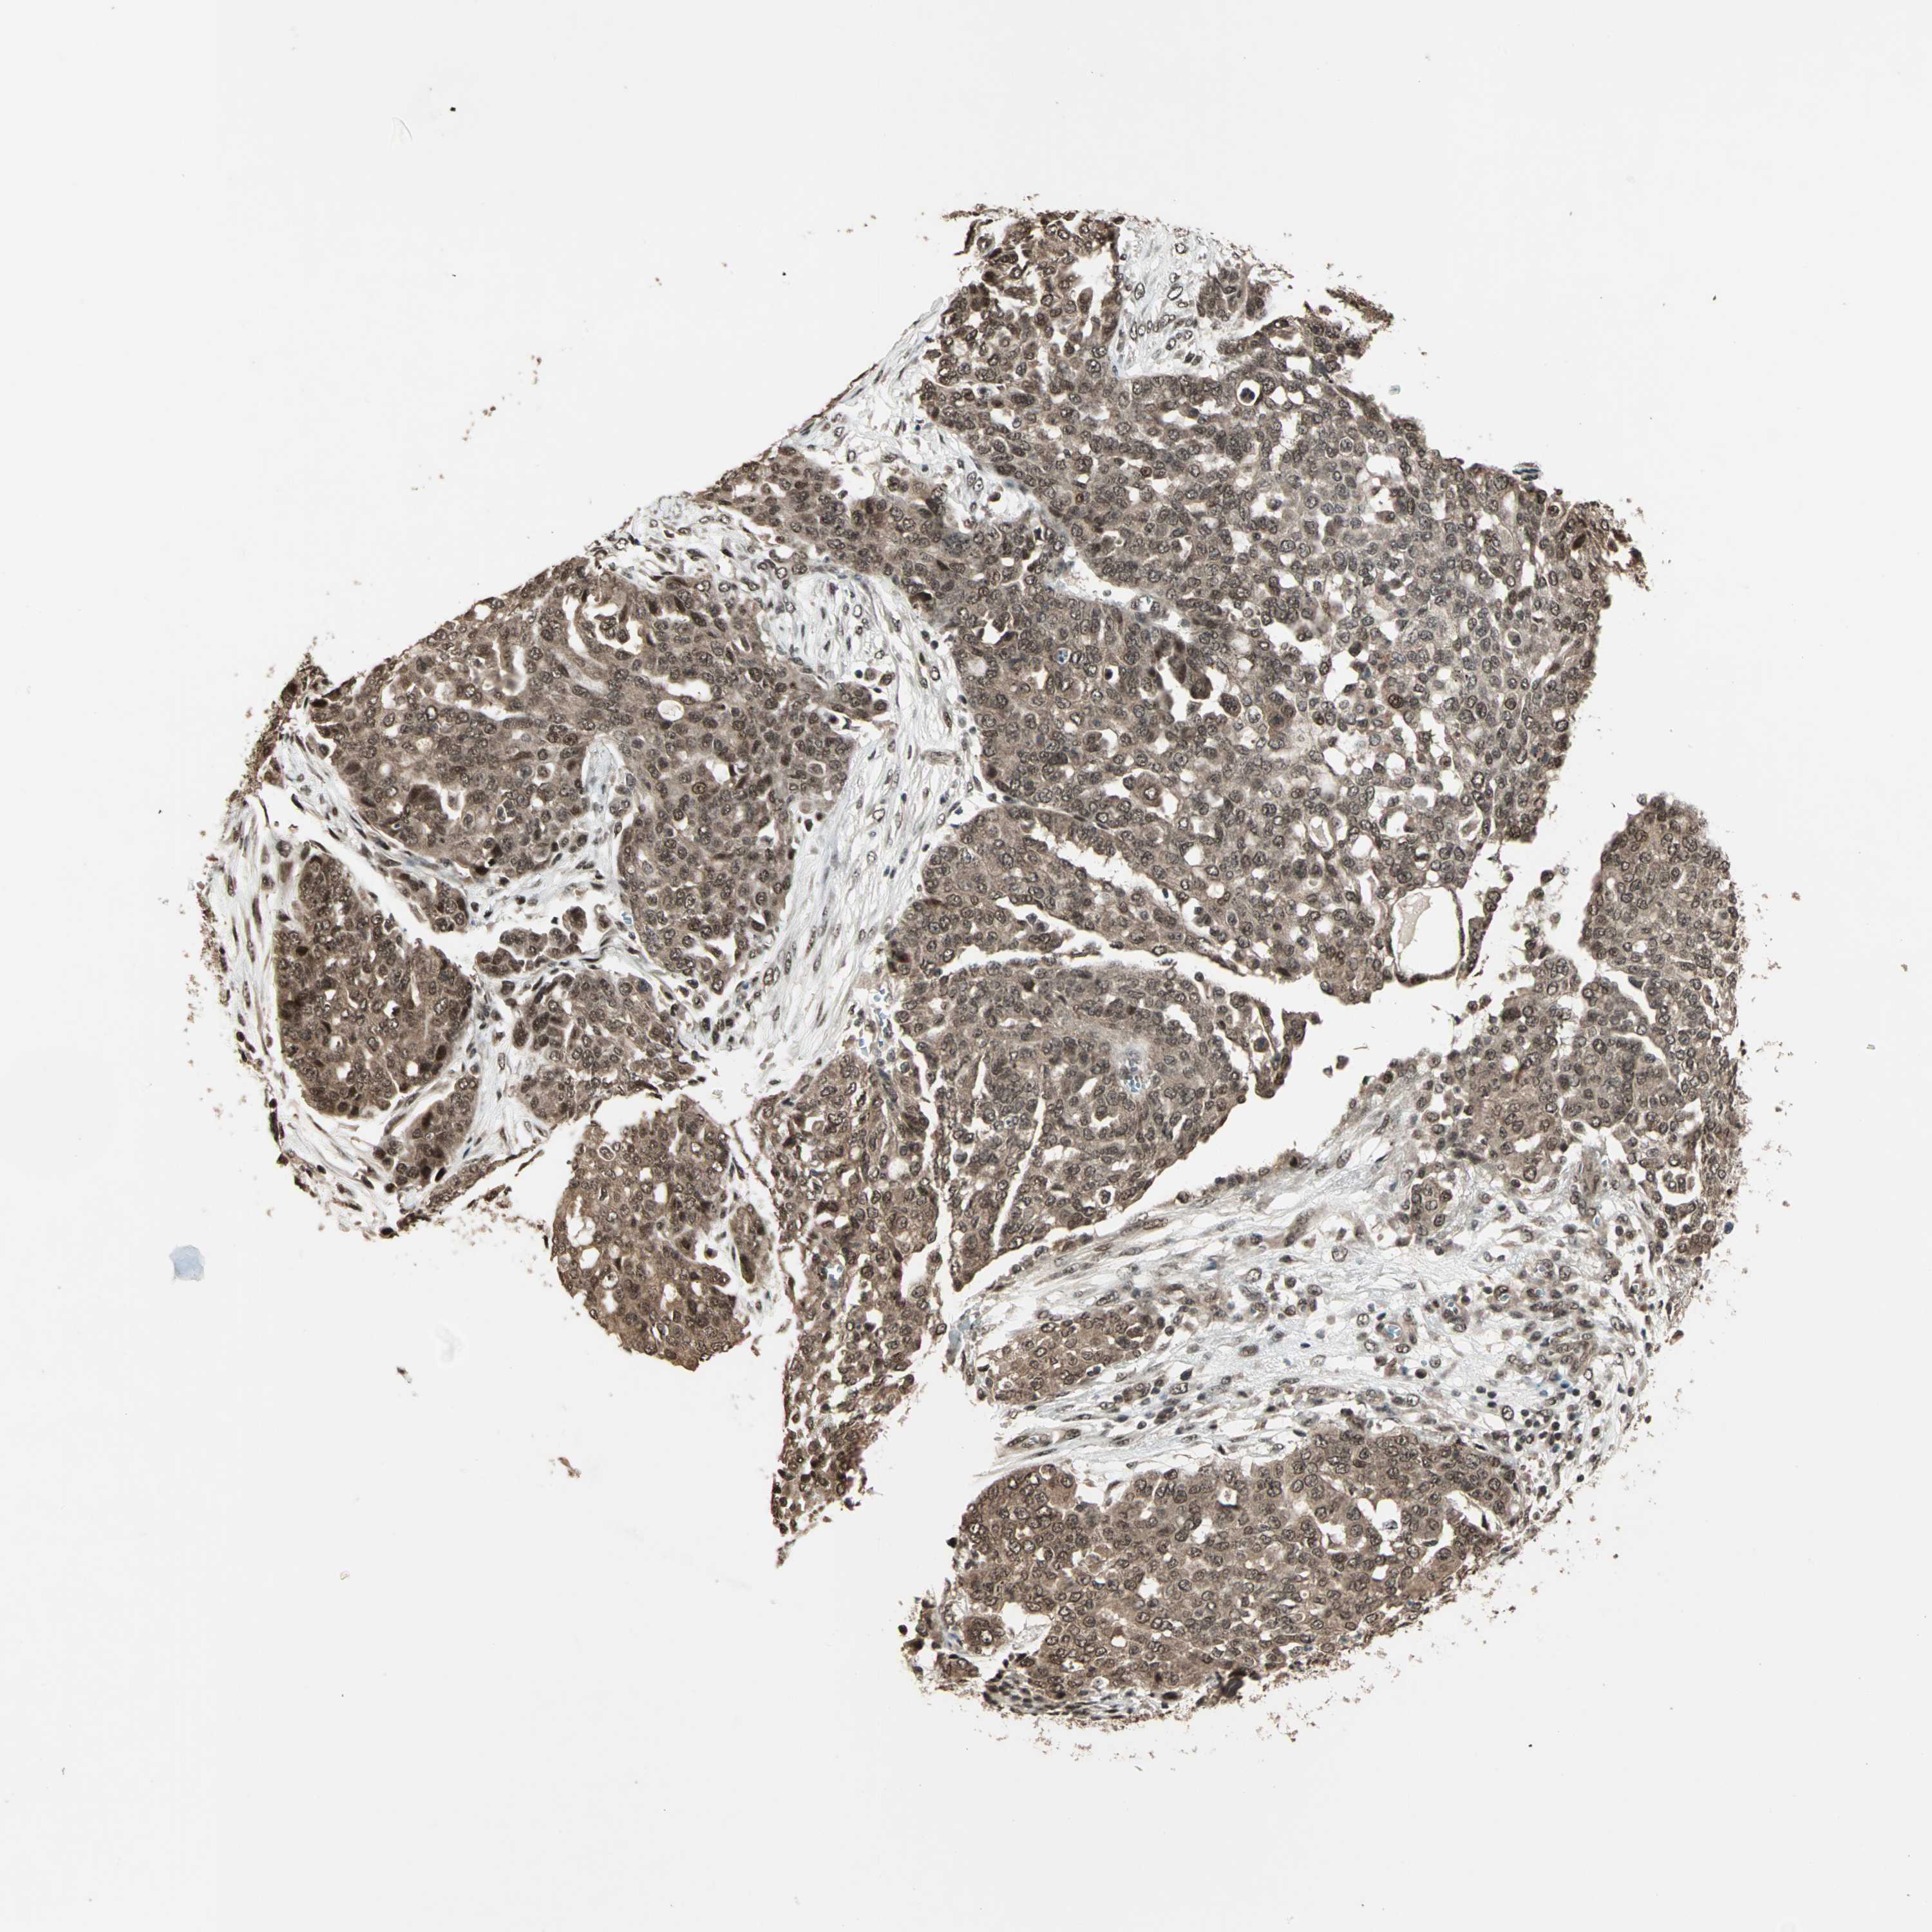

OVARIAN CANCER - Protein expressioni

A mouse-over function shows sample information and annotation data. Click on an image to view it in a full screen mode. Samples can be filtered based on level of antibody staining by selecting one or several of the following categories: high, medium, low and not detected. The assay and annotation is described here.

Note that samples used for immunohistochemistry by the Human Protein Atlas do not correspond to samples in the TCGA dataset.

Antibody stainingi

Antibody staining in the annotated cell types in the current human tissue is reported as not detected, low, medium, or high, based on conventional immunohistochemistry profiling in selected tissues. This score is based on the combination of the staining intensity and fraction of stained cells.

Each image is clickable and will lead to virtual microscopy that enables deeper exploration of all samples and also displays staining intensity scores, fraction scores and subcellular localization as well as patient and tissue information for each sample.

Antibody HPA003146

Staining

High

Medium

Low

Not detected

Intensity

Strong

Moderate

Weak

Negative

Quantity

>75%

75%-25%

<25%

None

Location

Nuclear

Cytoplasmic/membranous

Cytoplasmic/membranous,nuclear

Cystadenocarcinoma, serous, NOS

Carcinoma, endometroid

Carcinoma, NOS

Cystadenocarcinoma, mucinous, NOS